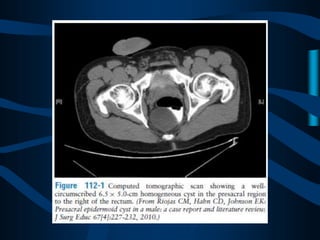

INDICACIONES EVALUACIÓN Y MANEJODEL DOLOR PERIANAL, RECTAL Y GENITAL, SÍNDROMES DOLOROSOS BENIGNOS COMO ENDOMETRIOSIS, DISTROFIA SIMPÁTICO REFLEJA, PROCTALGIA, ENTERITIS POR RADIACIÓN.